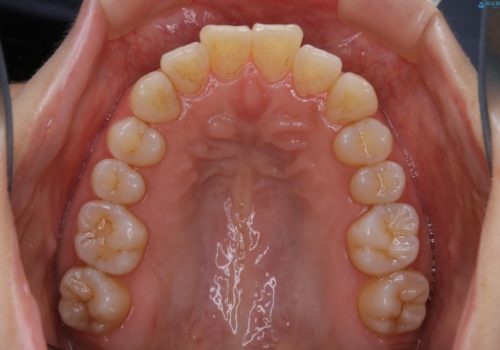

インビザライン・ライトでの抜歯矯正治療 (スリーインサイザー仕上げ)

- 上下の前歯のがたつきが気になるとのことで来院されました。最短治療とインビザラインでの矯正治療をご希望されました。

前歯のがたつきを無くすためには、スペースを確保する必要があります。上の前歯のがたつきは軽度ながたつきのため、歯と歯の間を研磨をして、そのスペースを使い並べていきます。下の前歯は、1本前歯を抜いて研磨せずに、その抜歯したスペースを使い並べることになりました。

インビザライン・ライトにて矯正治療を行うことになりました。

下の前歯は、スリーインサイザー仕上げと言って、通常前歯は4本ありますが(犬歯はいれていない)、そのどれか1本を抜歯して前歯を3本にして矯正治療を行うことを言います。また、先天的に歯の本数が少ない方もいますので、矯正治療を行っていなくても元々スリーインサイザーの方もいます。